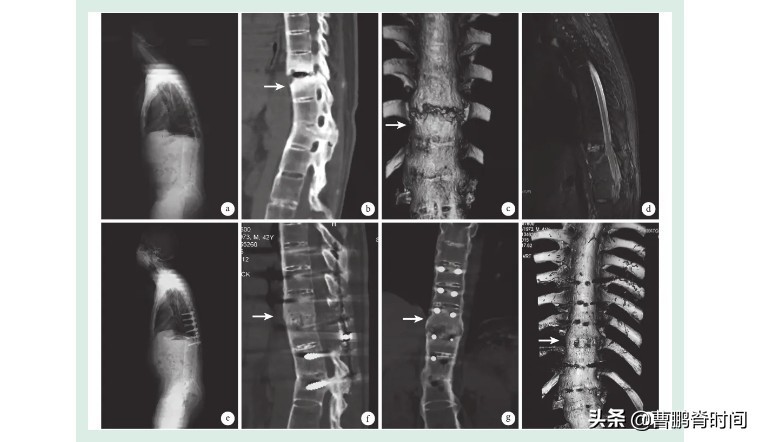

在我们外科手术台上躺着的强直患者,他们的脊柱都是下面这个样子:

所谓强直,就是在炎症因子的作用下,脊柱的各个节段慢慢被融合,形成一种类似于竹节似的改变。

患者会感觉自己的后背像是被水泥填满一样,脊柱仿佛是一根硬邦邦的棍子,不能随意弯折和伸展。

伴随着骨密度的加速流失,他们的骨头会渐渐脆弱得像“瓷娃娃”,轻轻一掰就断。